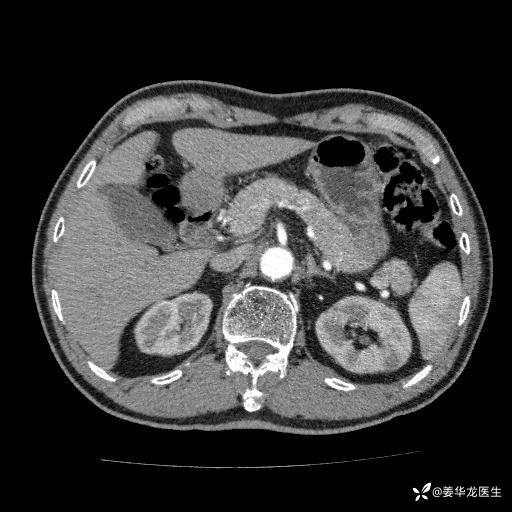

左肾中心型肾门部肿瘤39mm×34mm×36mm,右肾GFR25ml/min,部分切还是全切?

患者75岁老年男性,体重50kg,无高血压、肾病、糖尿病等基础病,检查发现左肾中心型肾门部肿瘤,右肾GFR只有25ml,无肉眼血尿,无镜下血尿。入院验血常规检查均正常,包括肾功能,肌酐102.7umol/L.

二、左肾肿瘤与左肾集合系、左肾动静脉关系密切,左肾部分切除术可行吗?成功率有多大?成功部分切后,肾功能还有多少?

四、左肾根治疗切除术后,透析的机率有多大?